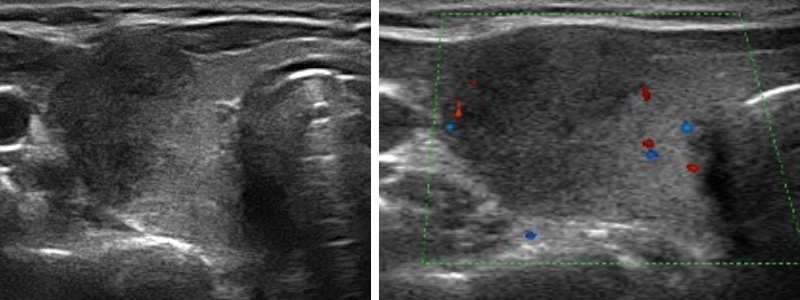

- contexte viral, douloureux

- plage hypoéchogène antéro-externe mal limitée peu vascularisée

- contrôle à M3 si pseudonodulaire